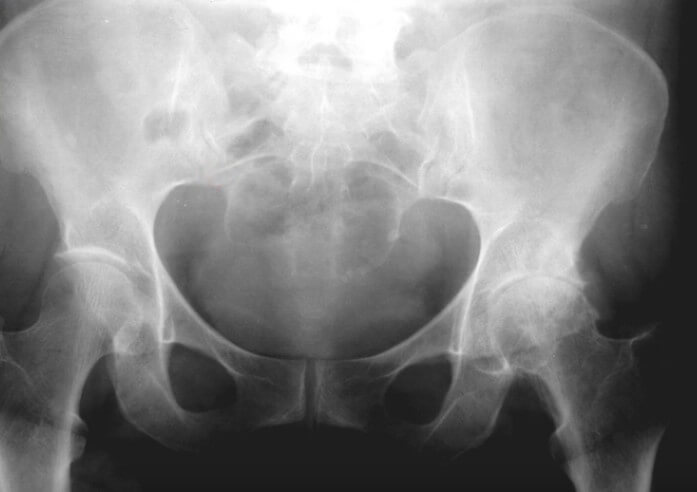

Сужение суставной щели, остеофиты, остеосклероз

Диагностика патологий в тазобедренном суставе при помощи рентгеновской визуализации немного сложнее в сравнении с диагностикой ОА коленного сустава. Тем не менее, при выполнении обзорной рентгенографии таза мы четко можем видеть сужение суставной щели тазобедренного сустава, остеофиты на краю головки бедренной кости, субхондральный остеосклероз в области головки бедренной кости и вертлужной впадины, перестройка структур костей, формирующих тазобедренный сустав.